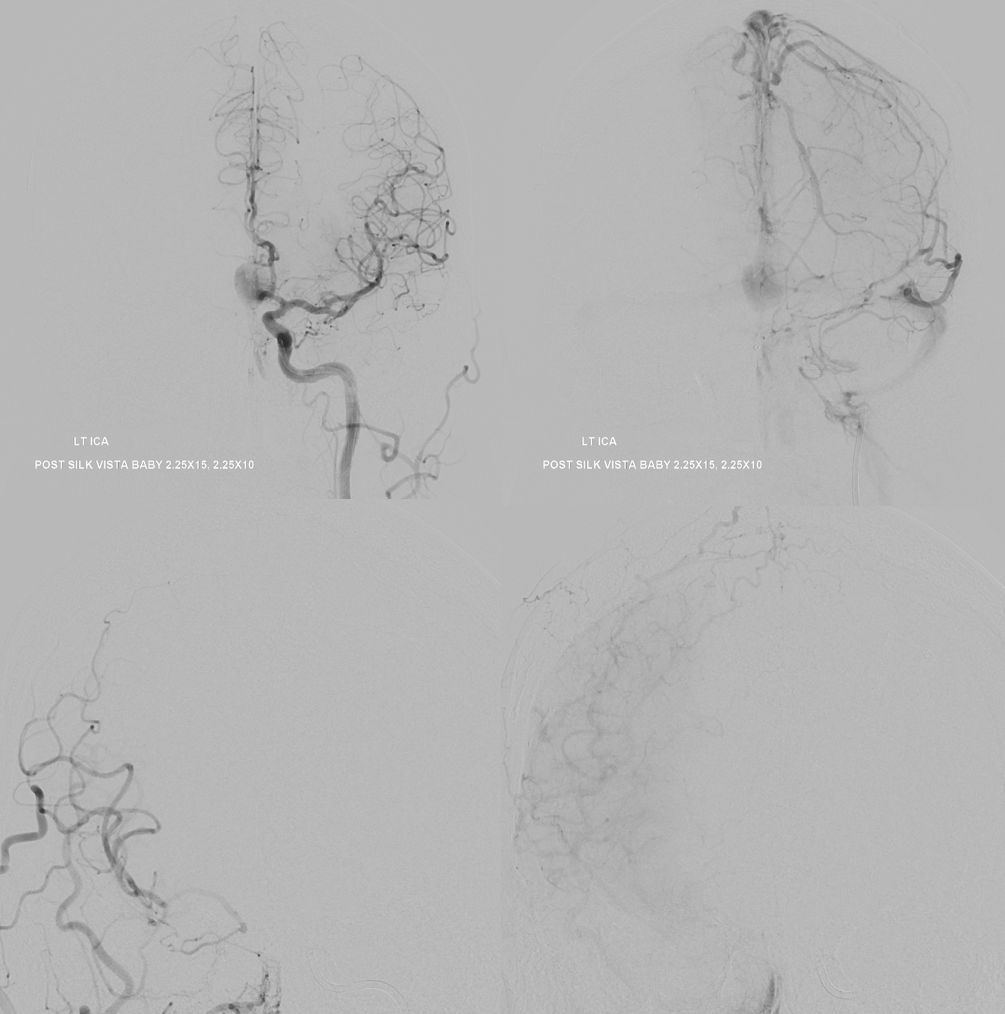

Post. Bilateral injections. The right ACA is supplied retrogradely via the ACA-ACA bypass. The MOST important finding here is that there is no longer flow across the ACOM. This is what flow modification is. Changing dynamics to impact aneurysm.

One month later — only 1 mo. Aneurysm thrombosed. Right A1-A2 patent — can tell on MRA even with two SVBs

Several months later, MRI looks fantastic — no edema, smaller, etc. This MRI is actually enough to know the aneurysm is gone. Its more sure than angio.

MRA